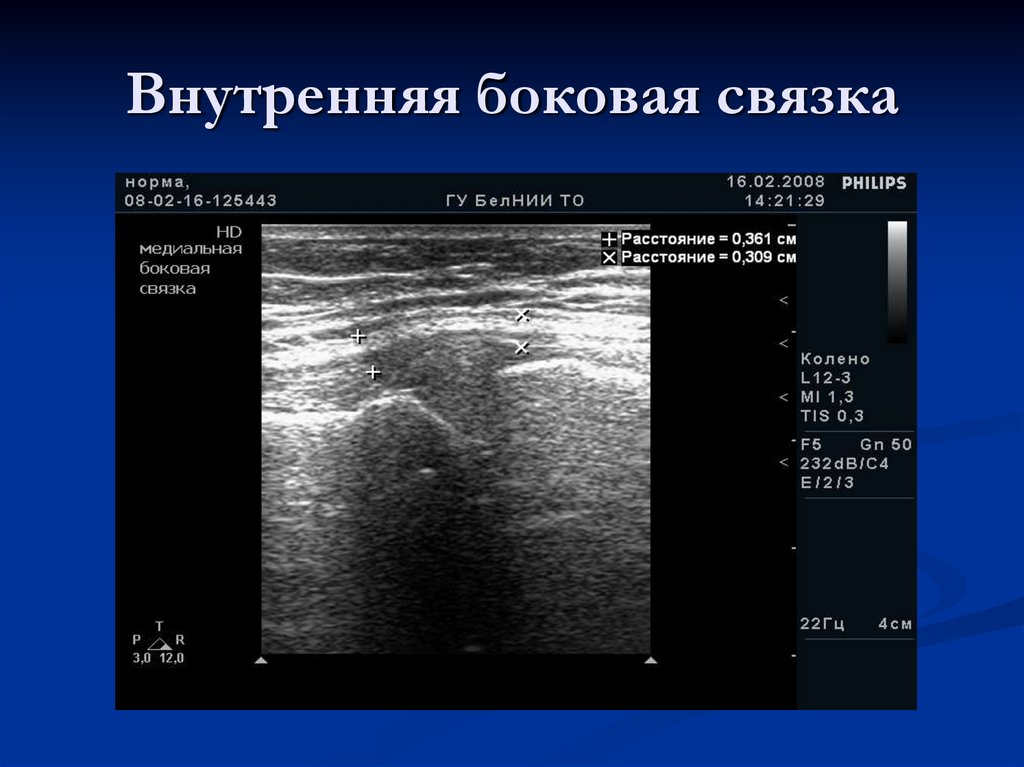

Внутренняя боковая связка

22. Передняя медиальная проекция

23. Передняя медиальная проекция

Внутренняя боковая

связка представлена

типичной для связки

эхоструктурой.

Передний рог

медиального мениска

виден неотчетливо

(стрелка)